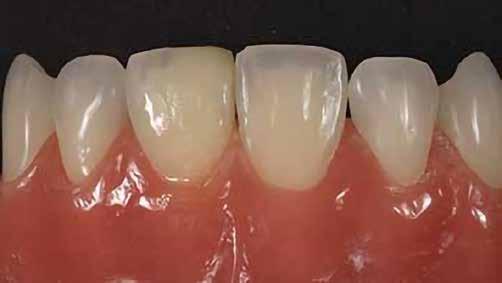

A betétek készítéséről készülök előadást tartani. Ez a terület hallgató korom óta tetszett, és mára a rendelőnkben végzett kezelések jelentős részét teszi ki.Héjkerámiák ragasztására váró fogak.

A fogászati kezelések során manapság már nem kizárólag az esztétikai megjelenés helyreállítására törekszünk. Sokszor a kedvezőtlen esztétikai megjelenés hátterében álló okok következményes módon a fogazat funkcionális működését is károsítják, így a kezelések során ezeknek a helyreállításával is foglalkoznunk kell. A különböző funkcionális és esztétikai diszkrepanciák kezelésére számtalan módszer létezik, ám ezen fogászati beavatkozások mindegyikében közös, hogy a kivitelezésük során nagyon szoros együttműködésre van szükség a kezelést végző fogorvos és a munkáját segítő fogtechnikus között. Az alábbi esetbemutatás során egy fiatal hölgypáciens fogazatának héjak alkalmazásával történő esztétikai és funkcionális rehabilitációját szeretnénk ismertetni.

A páciens fogazata esztétikai megjelenésének és funkcionális működésének a lehető legtöbb, saját foganyag megtartása mellett történő helyreállítása (1. és 3. ábra).